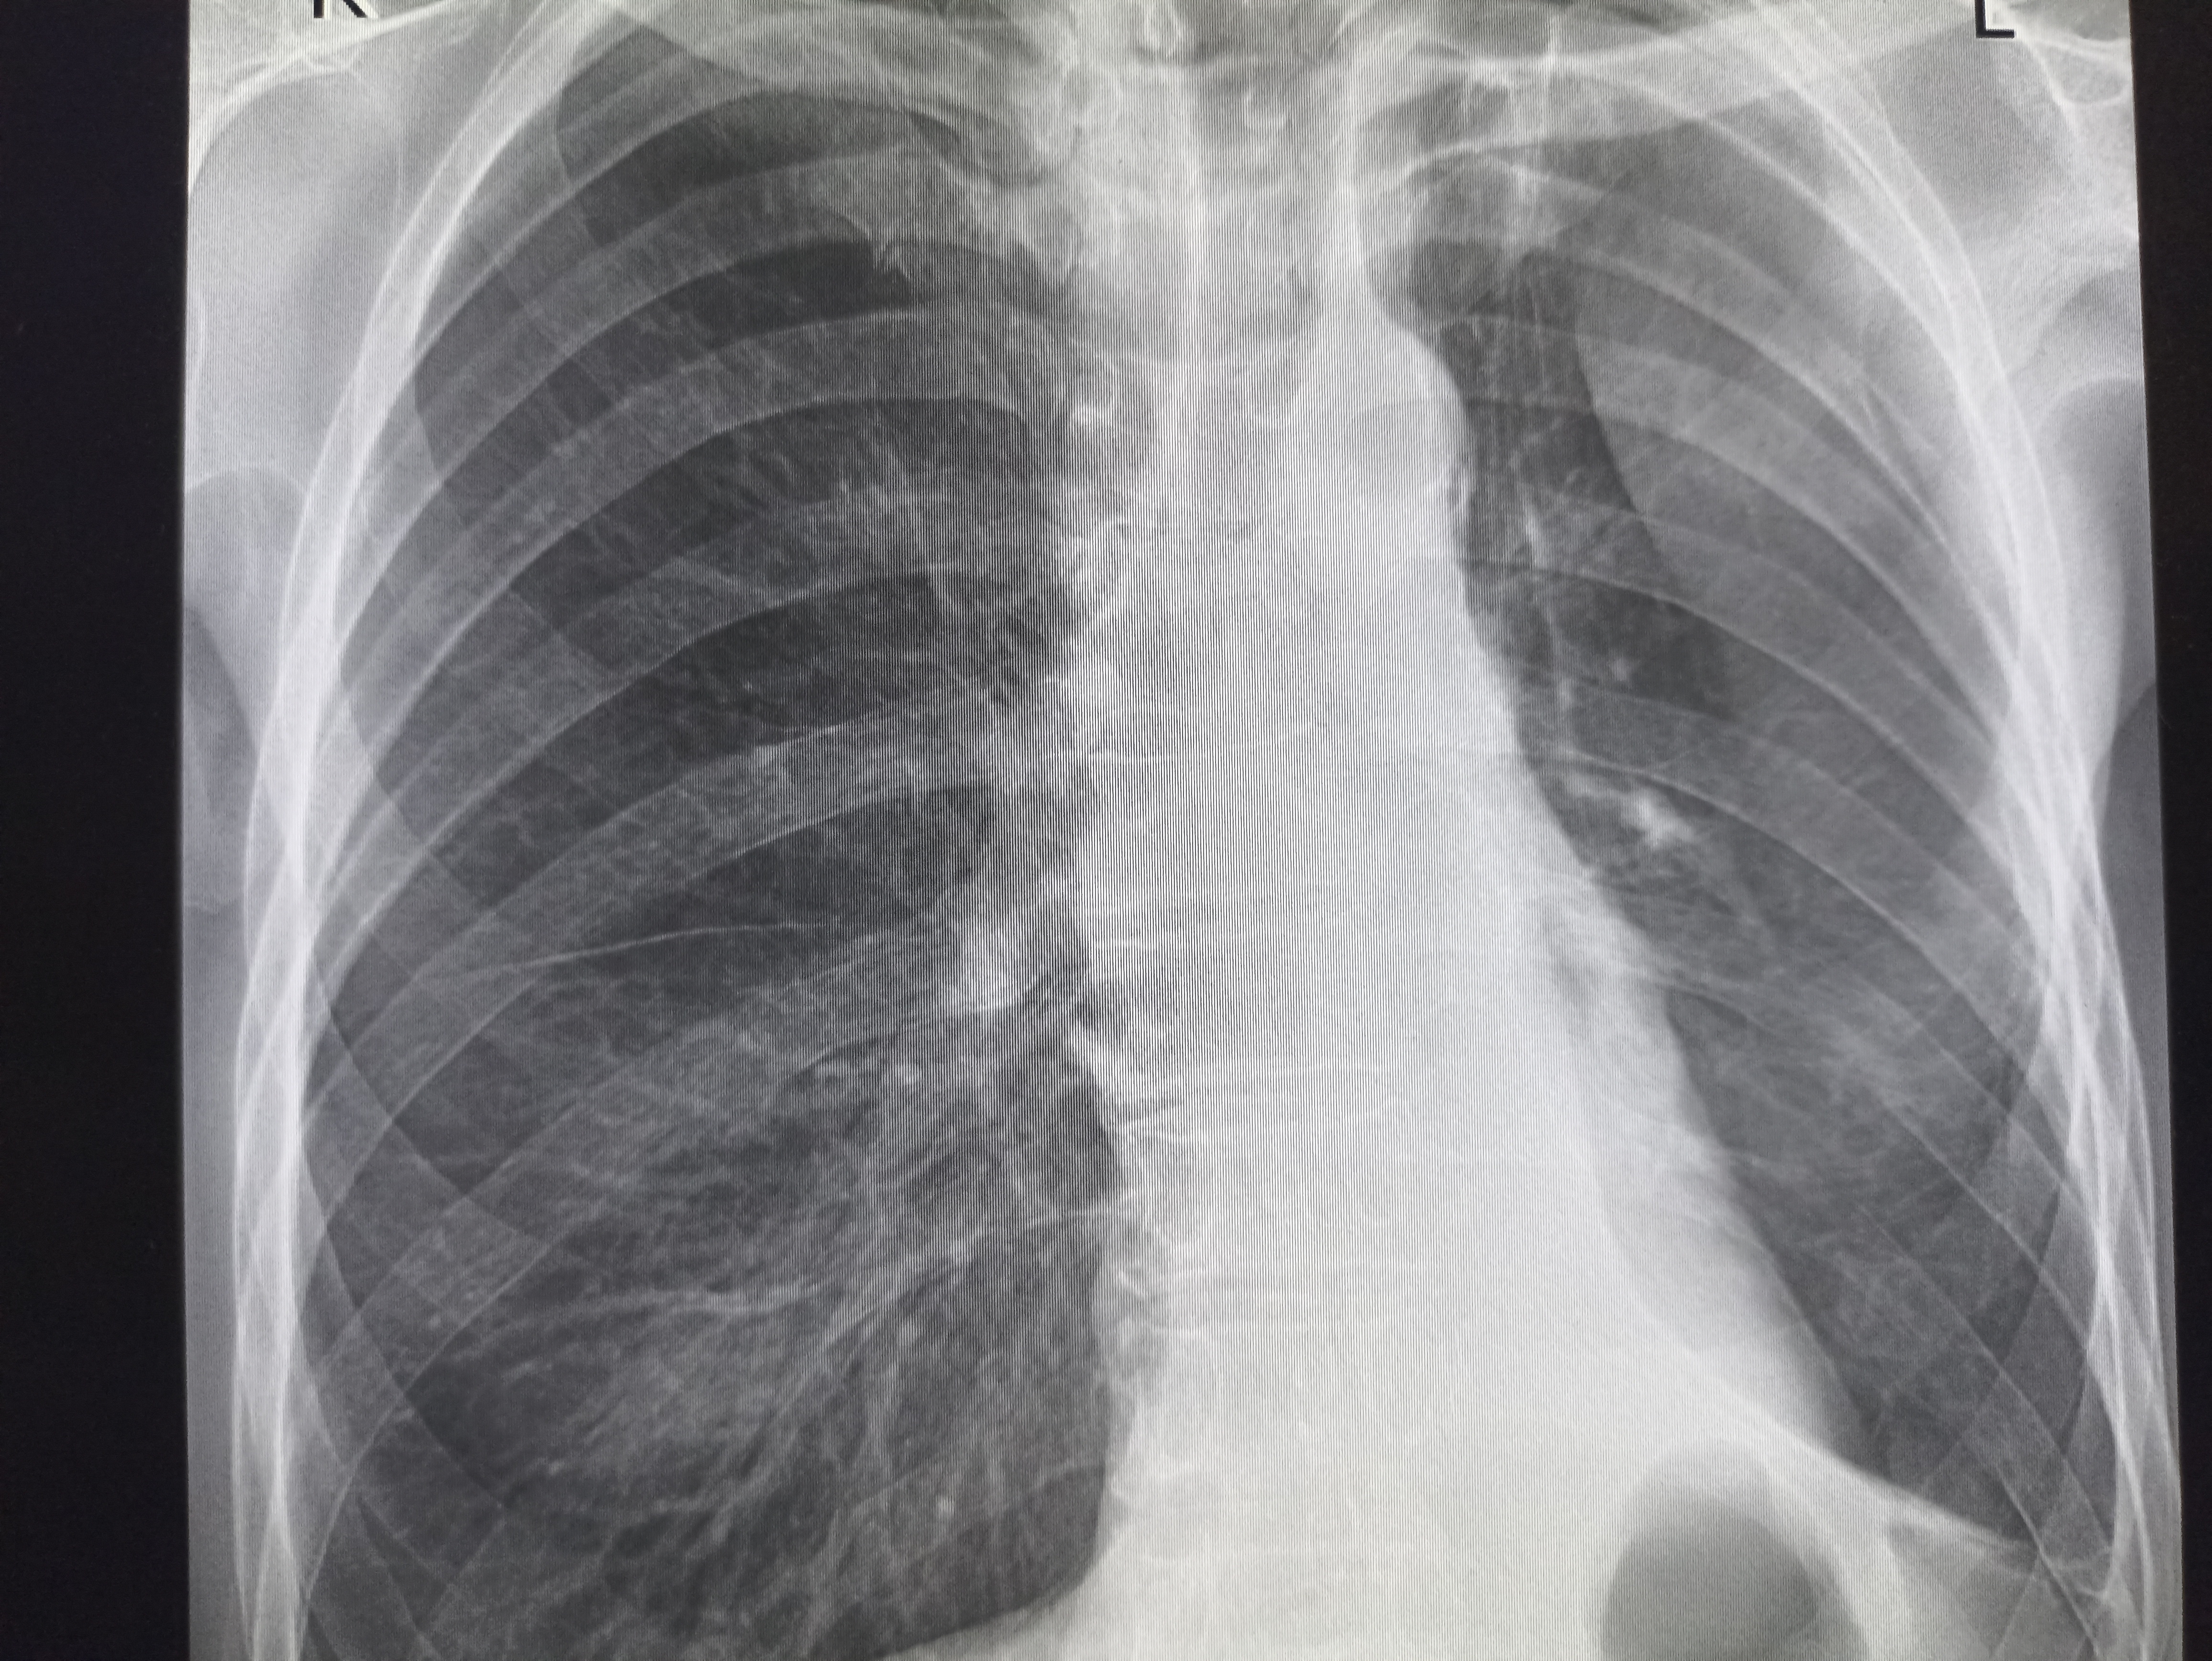

IMG20251208112948.jpg

Где пиздецома?

>>327474821

Пневмония в нижнем сегменте.

Ну или тубер

>>327475007

Там еще жижа и плеврит

>>327475010

Бля пиздец фу гадость. Он уже лежит где-то или на своих двоих прищел?

Дренаж?

>>327475034

Пунктировали два раза уже. Приехал из поликлиники в приемник. Он там всяким по вене ставился и у него него не ток в легких все фу неоч.

Гидроторакс с линией демуазо?

>>327475343

Ну чот, а метастазы чому игноришь?

>>327474838

Округлое образование с проветлением в центре в нижней доле правого лёгкого. На тубик не похоже по локализации, мб абсцесс в стадии рассасывания

>>327474857

Бля то ли субтотальная пневмония, то ли осумкованный плеврит такой. всё нахуй забыл уже с рентгенологии

>>327475456

Тут просто гидроторакс, там недостаточность по большому кругу